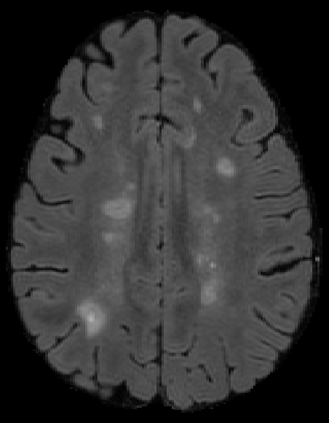

The detection of new multiple sclerosis (MS) lesions is an important marker of the evolution of the disease. The applicability of learning-based methods could automate this task efficiently. However, the lack of annotated longitudinal data with new-appearing lesions is a limiting factor for the training of robust and generalizing models. In this work, we describe a deep-learning-based pipeline addressing the challenging task of detecting and segmenting new MS lesions. First, we propose to use transfer-learning from a model trained on a segmentation task using single time-points. Therefore, we exploit knowledge from an easier task and for which more annotated datasets are available. Second, we propose a data synthesis strategy to generate realistic longitudinal time-points with new lesions using single time-point scans. In this way, we pretrain our detection model on large synthetic annotated datasets. Finally, we use a data-augmentation technique designed to simulate data diversity in MRI. By doing that, we increase the size of the available small annotated longitudinal datasets. Our ablation study showed that each contribution lead to an enhancement of the segmentation accuracy. Using the proposed pipeline, we obtained the best score for the segmentation and the detection of new MS lesions in the MSSEG2 MICCAI challenge.